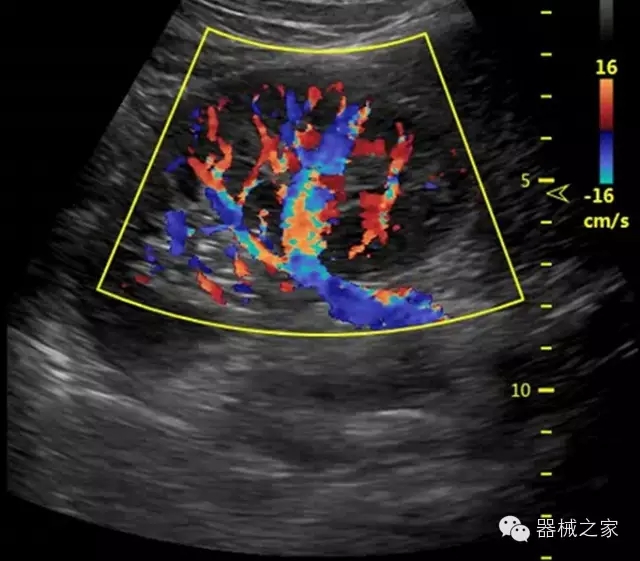

臨床圖片賞析

·智能感知組織特異性的VTissue技術(shù),結(jié)合特有高達(dá)22MHzXcen線陣探頭, 以及獨(dú)有敏感的RF射頻血流提供了優(yōu)異臨床圖像;

·獨(dú)有RF敏感血流使得心臟血流完美呈現(xiàn);